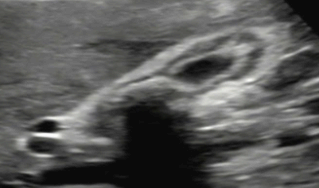

US finding

- 담낭주위 띠모양의 경계가 좋은 액체저류가 보인다

- 담낭은 경계가 불분명해지며 팽팽해진다

- 심한 경우 저에코성 종괴들이 관찰된다